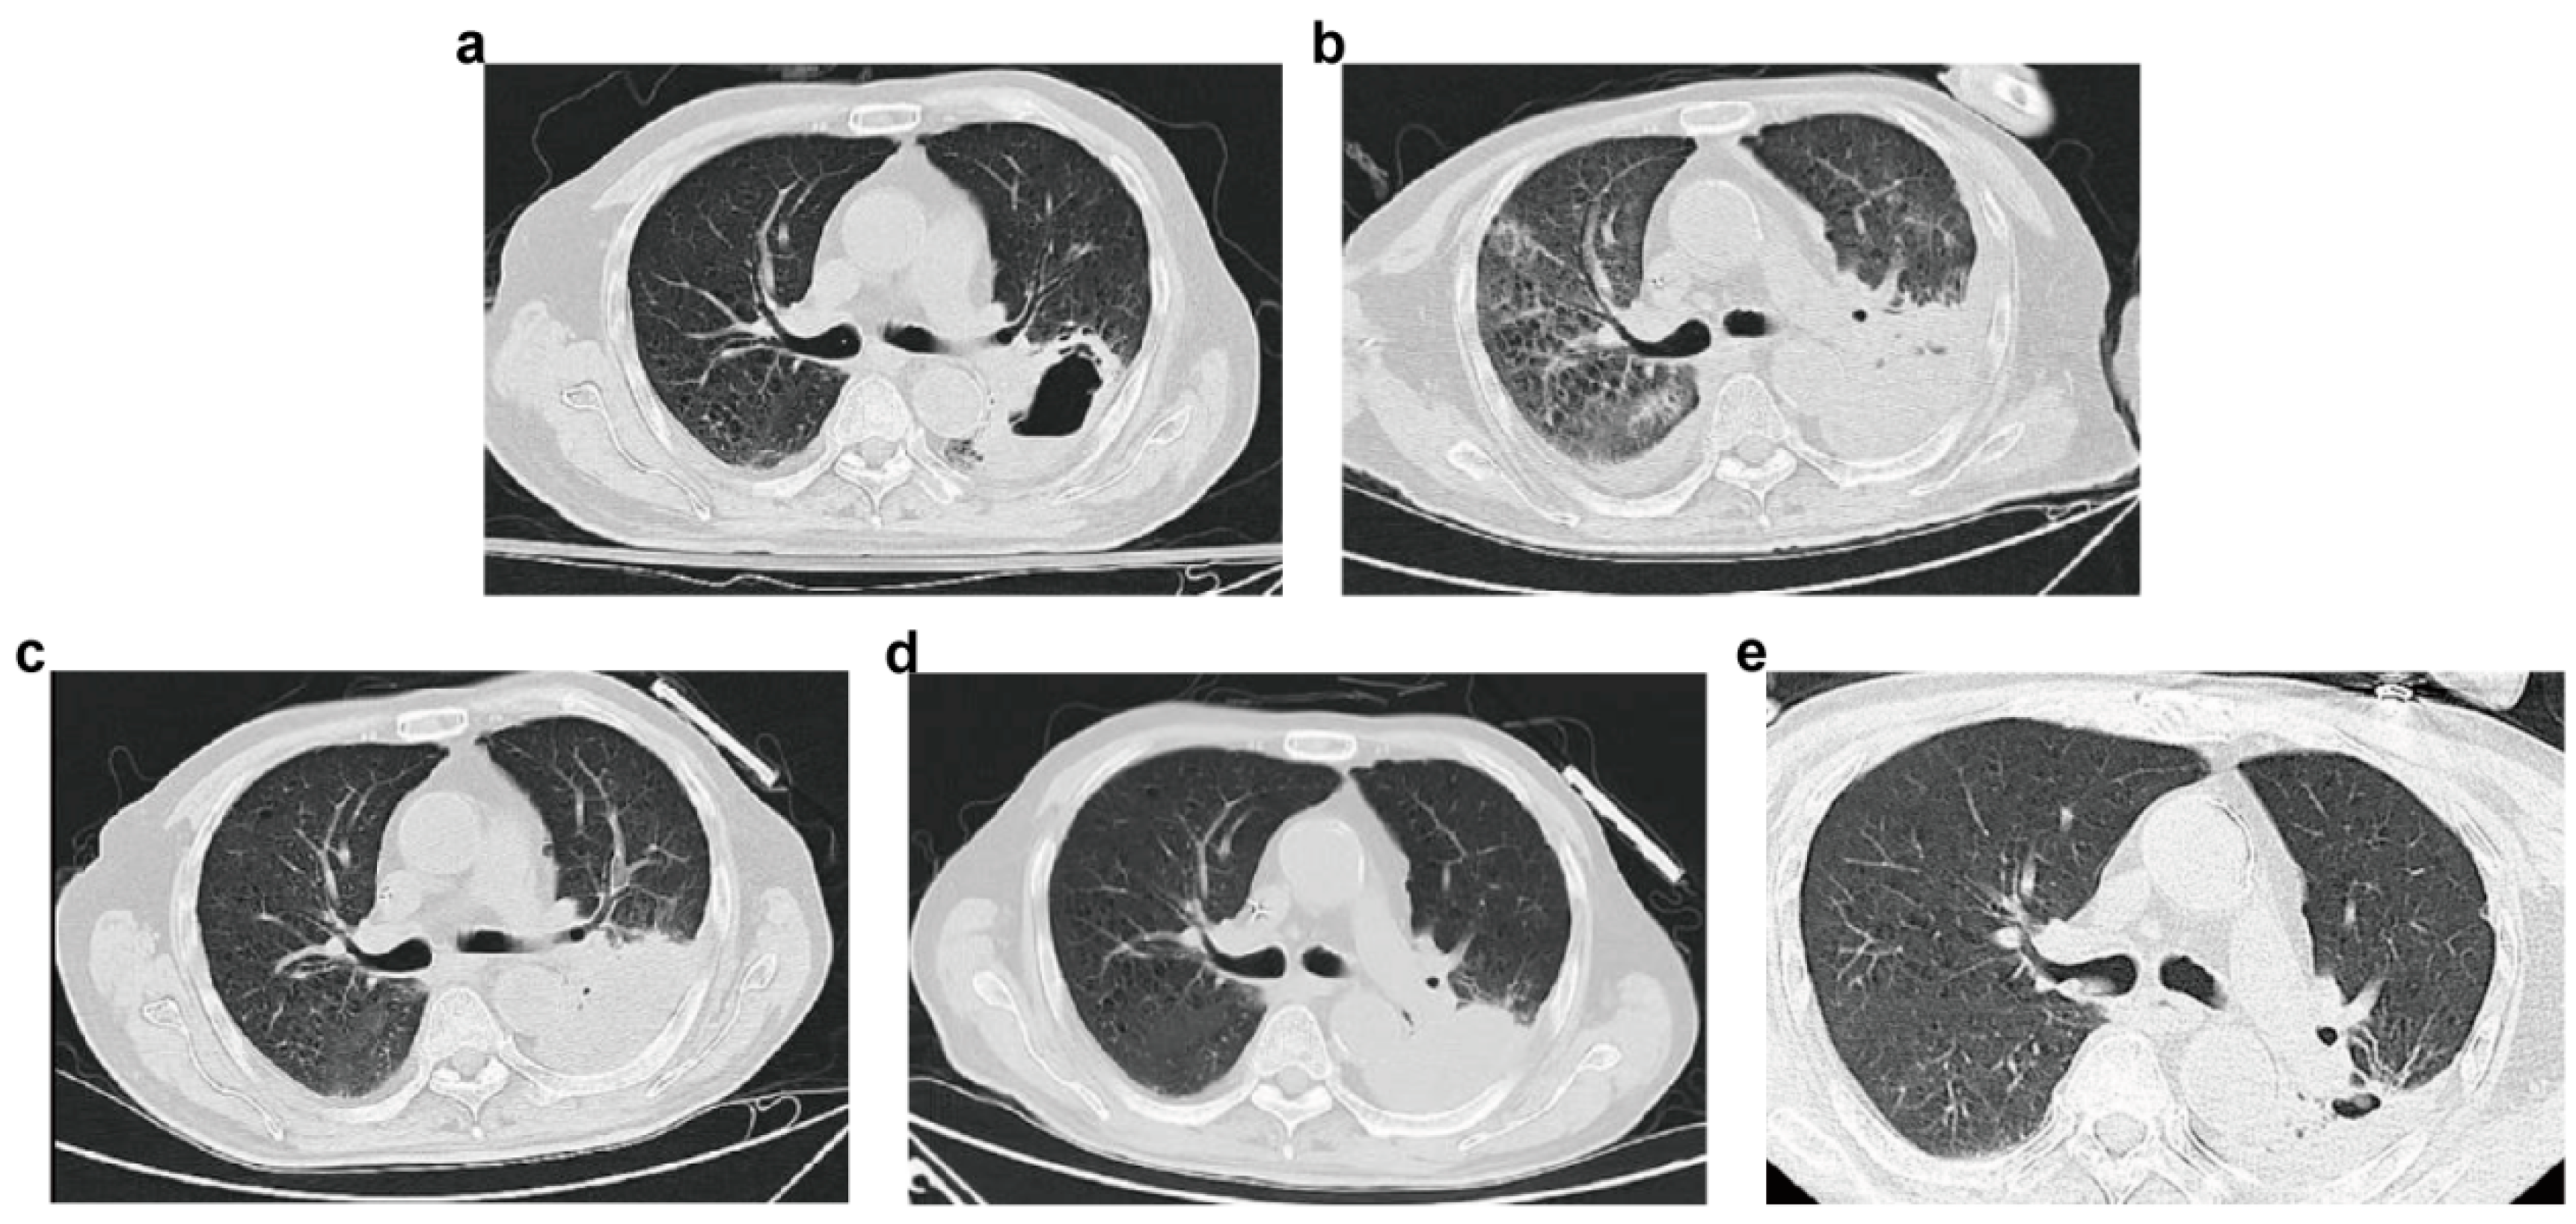

2. Case Report